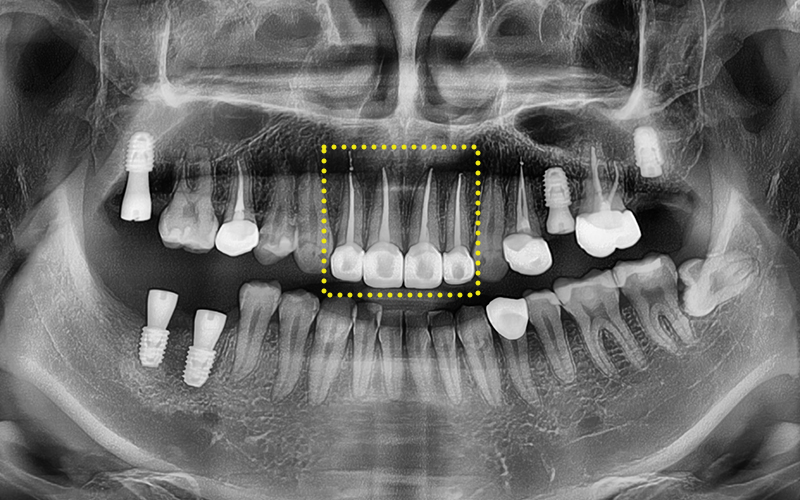

A panoramic X-ray was taken

to perform a detailed check,

and an overall treatment plan was established.

As can actually be seen in the treatment record,

more than 10 teeth received

root canal treatment,

and most were accompanied by complex inflammation and nerve infection.

In particular, treatment was carried out across a wide area,

including the upper front teeth and molars.

You can also check on the panoramic image

that the treatment was carried out successfully.

Currently, the implant is in a state where only the fixture,

which is the artificial root part,

has been placed,

and we plan to complete the prosthetic process

by later placing the crown (prosthesis).